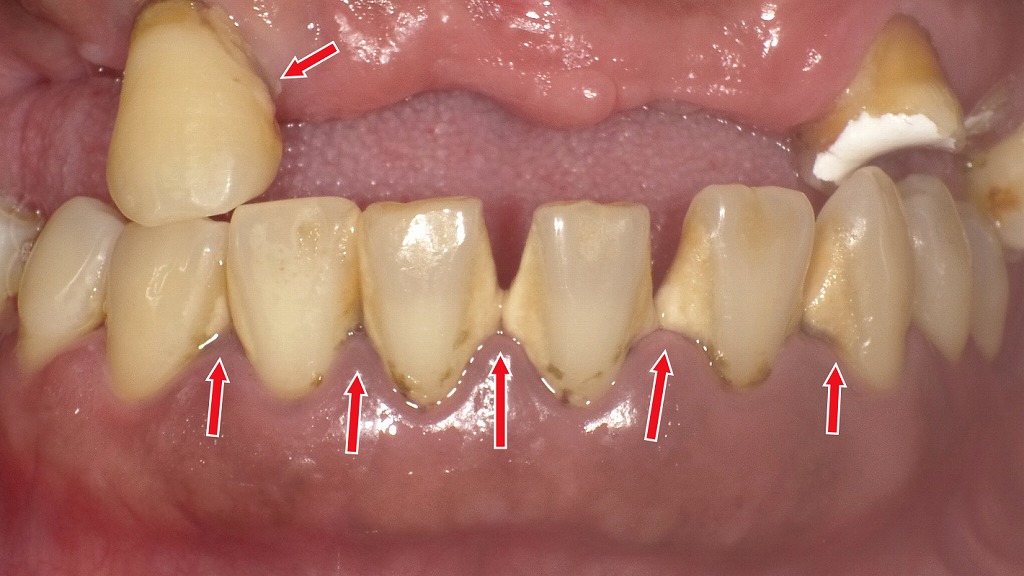

放置した歯石が噛み合わせ痛の引き金に

前歯の根元に大量の歯石が付着し、歯ぐきが強く炎症を起こしている状態です。炎症によって歯を支える組織が弱くなるため、噛んだときに痛みが出たり、歯が浮いたように感じたりする原因になります。ブラッシングでは取れない歯石のため、歯科医院での専門的なクリーニングが必要です。早期の歯石除去は、痛みの軽減と歯周病の進行予防につながります。